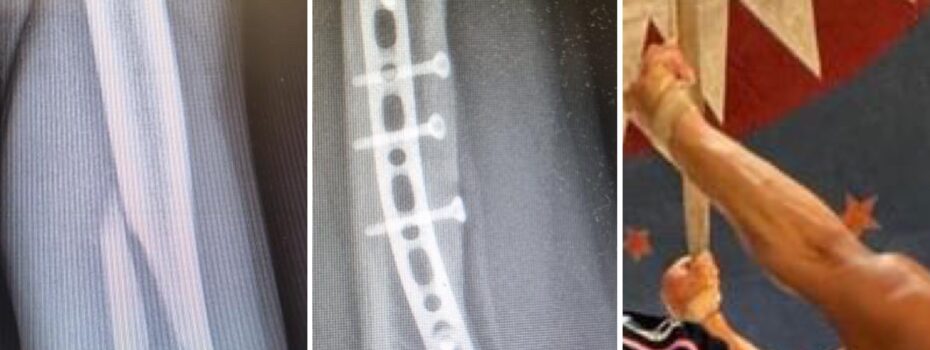

Dopo sei mesi di recupero, un giovane trapezista della famiglia Orfei, è tornato ad allenarsi e si prepara a riprendere i suoi spettacoli. Il quattordicenne aveva subito una frattura dell’omero durante l’esecuzione di un numero acrobatico estremamente difficile ed è stato operato presso l’ospedale Giovanni XXIII di Bari. “L’intervento è stato delicato, ha previsto l’applicazione […]